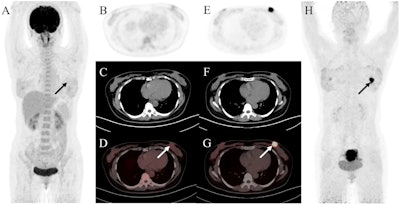

A 47-year-old woman was admitted with a left breast mass. For staging, the patient underwent F-18 FDG-PET/CT. The maximal intensity projection image (A) and the axial views (B: PET image; C: CT scan; D: PET/CT fused image) revealed normal findings. Then she underwent Ga-68 FAPI-PET/CT. The left breast showed intense uptake on Ga-68 FAPI-PET/CT (E: PET image; F: CT scan; G: PET/CT fused image; H: MIP, solid arrow; SUVmax, 15.4). Subsequently, the patient underwent pathology confirmed invasive lobular carcinoma of the left breast. Image and caption available for republishing under Creative Commons license (CC BY 4.0 DEED, Attribution 4.0 International) and courtesy of Cancer Imaging.